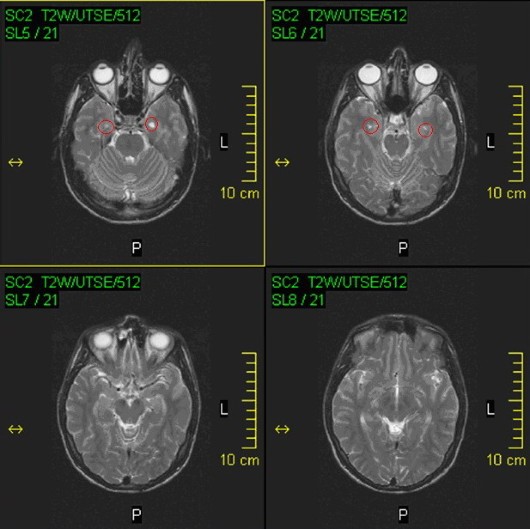

Stwardnienie rozsiane oznacza bliznowacenie tkanki nerwowej, która jest losowo rozmieszczona w układzie nerwowym.

Badania MRI z lat 1998–2006 wskazują na pogorszenie mojego stanu, ale później nastąpiła stabilizacja. Dzięki wykorzystaniu kannabinoidów (THC i CBD) mogłem łagodzić skutki uboczne leków, takie jak nudności, utrata apetytu, zaburzenia snu i drgawki.

STWARDNIENIE ROZSIANE

Stwardnienie rozsiane (SM) to choroba autoimmunologiczna ośrodkowego układu nerwowego. Układ odpornościowy atakuje osłonki mielinowe nerwów, co prowadzi do zaburzeń przewodzenia impulsów.